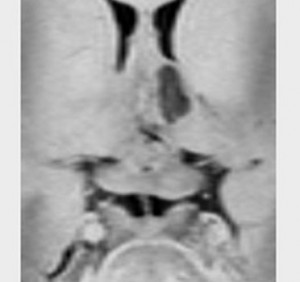

8歳で身長の伸びが悪くなり3年間診断されませんでした。12歳時に軽度の尿崩症を併発して発見されたものです。下垂体前葉機能はGH不全の他にはありません。

非常に典型的な下垂体後葉germinomaの画像です。萎縮して残った前葉線組織が前方にありガドリニウム増強されます。薄く増強されているトルコ鞍背部がgerminomaです。経蝶形骨洞手術で下垂体底面をもちあげて生検を行いました。